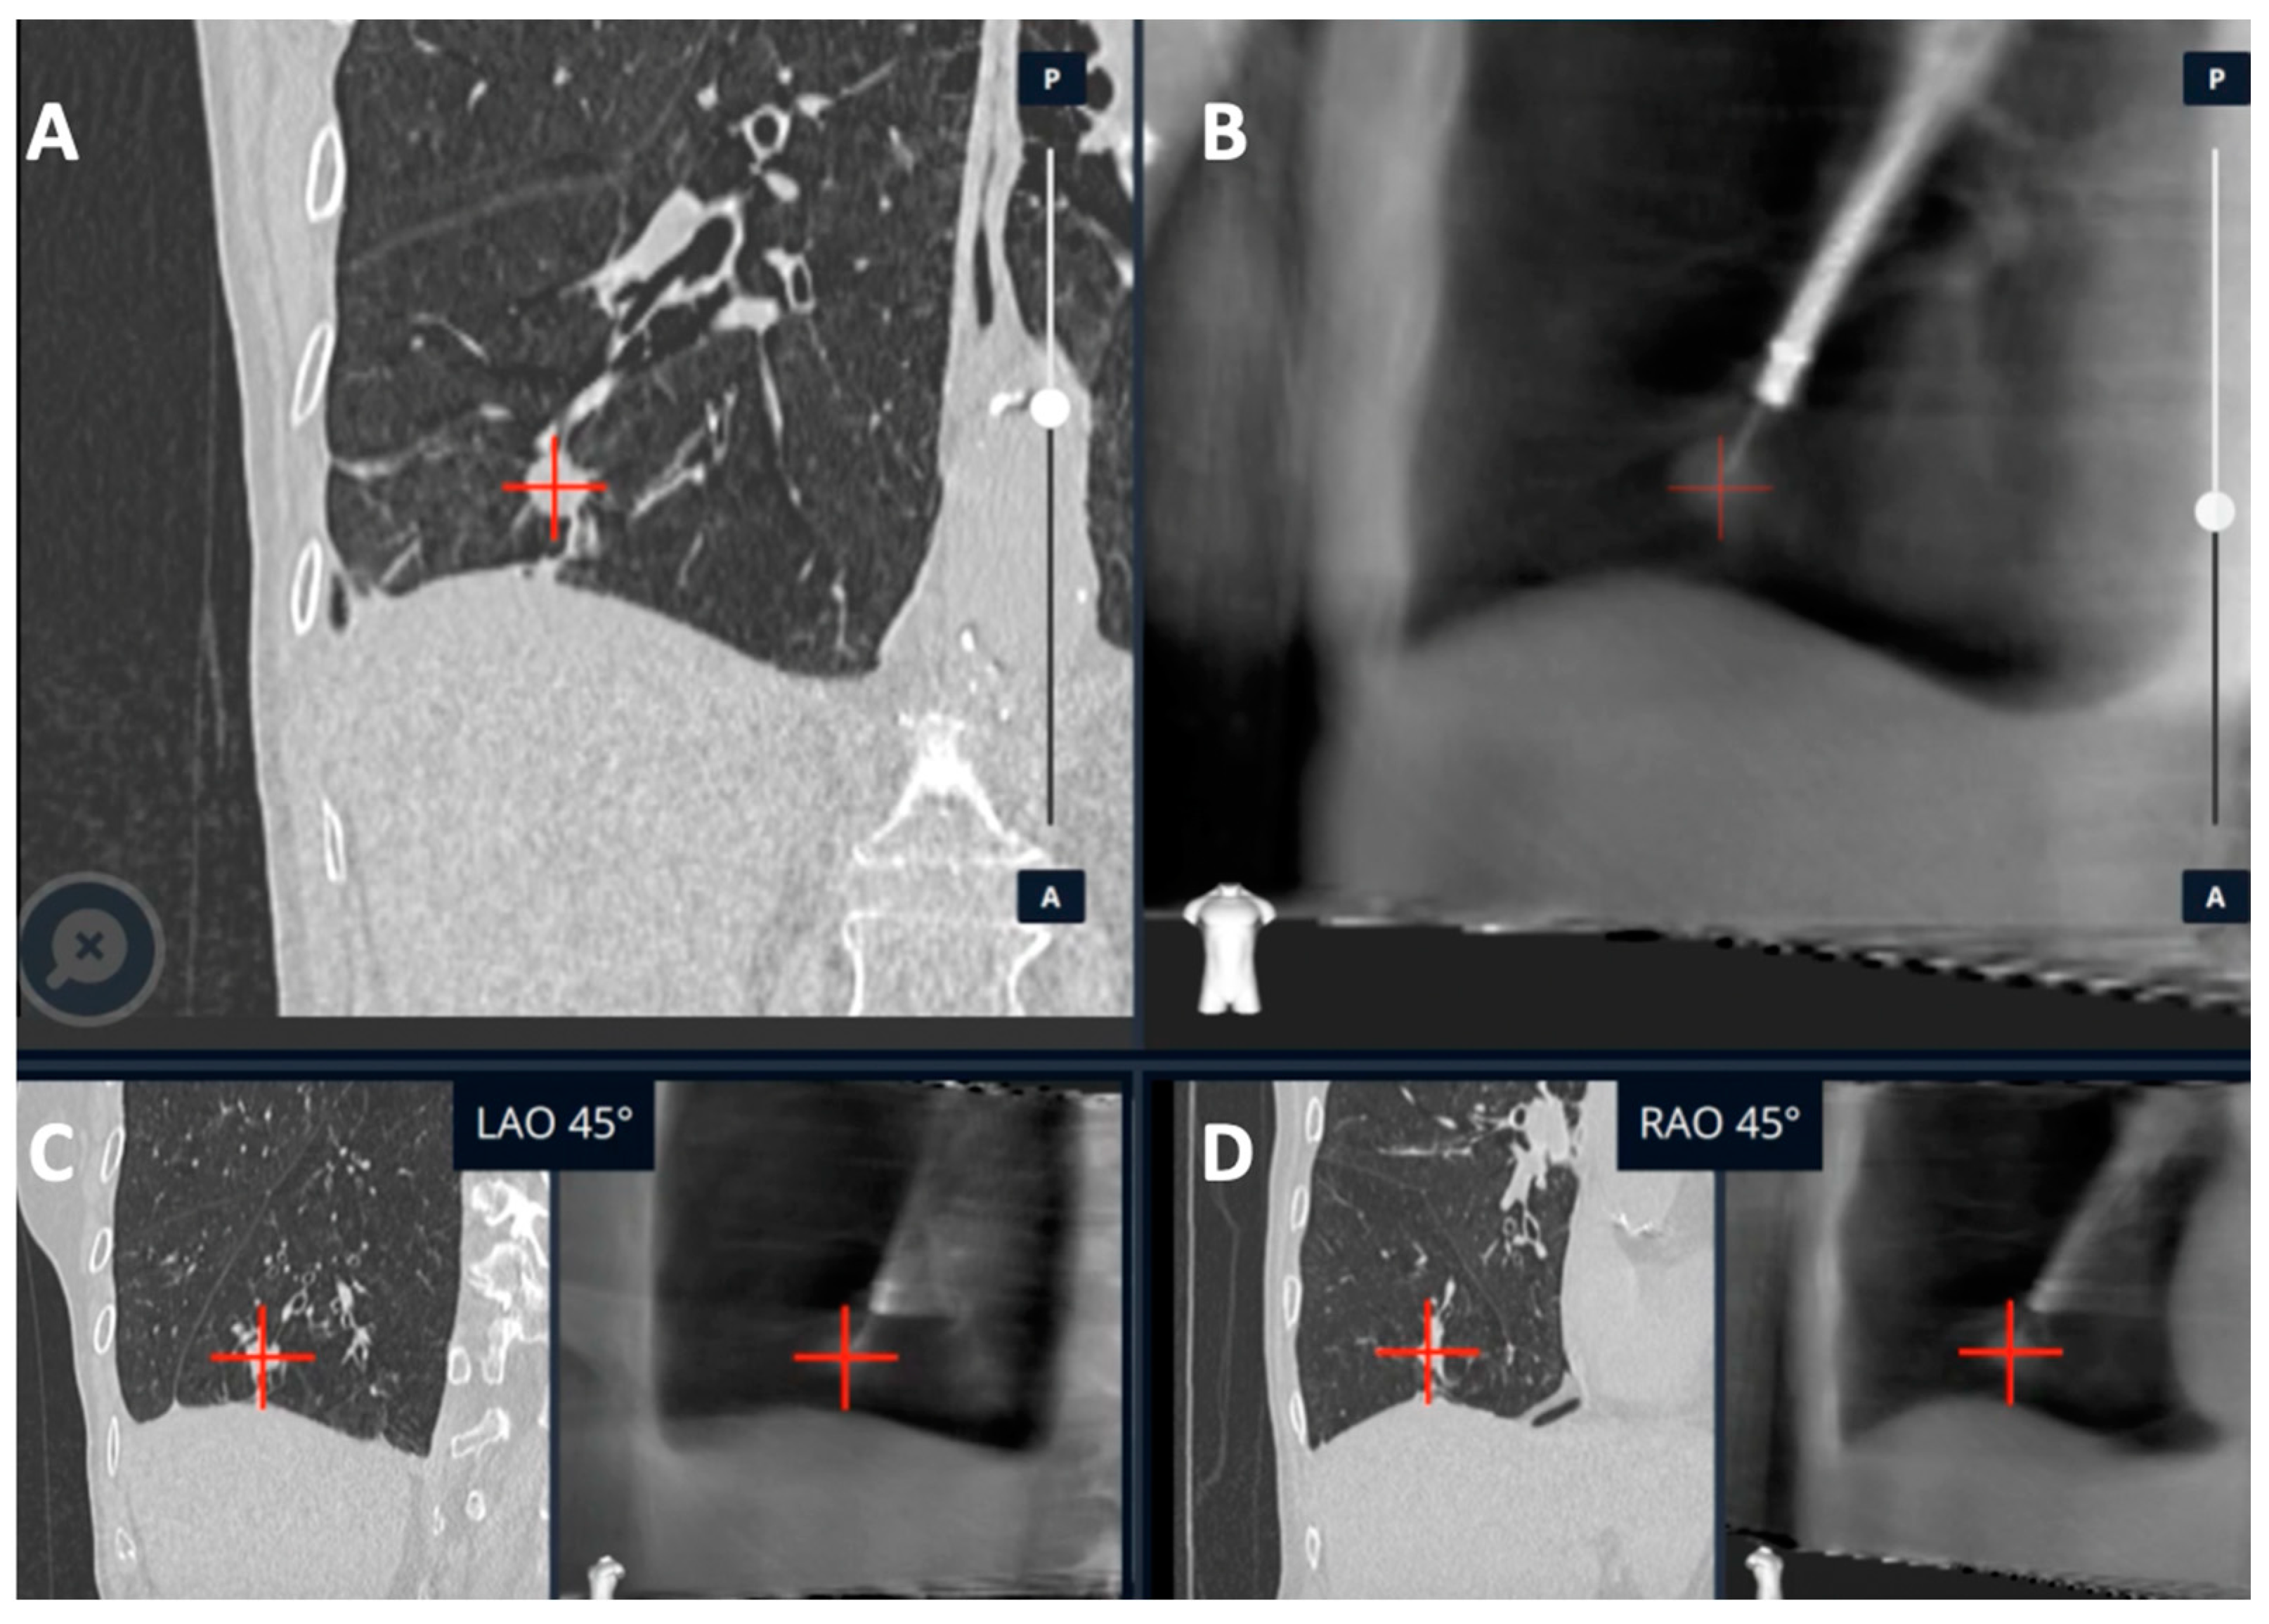

- Hedstrom, G.; Wagh, A.A. Combining Real-time 3-D imaging and augmented fluoroscopy with robotic bronchoscopy for the diagnosis of peripheral lung lesions. Chest 2022, 162, A2082. [Google Scholar] [CrossRef]

- Kalchiem-Dekel, O.; Fuentes, P.; Bott, M.J.; Beattie, J.A.; Lee, R.P.; Chawla, M.; Husta, B.C. Multiplanar 3D fluoroscopy redefines tool-lesion relationship during robotic-assisted bronchoscopy. Respirology 2021, 26, 120–123. [Google Scholar] [CrossRef] [PubMed]

| Kalchiem-Dekel et al. [20] | Ion™ robotic platform with CIOS | Robotic platform for navigation with 3D multiplanar fluoroscopy for intra-procedural real-time guidance | 10 lesions | Tool in lesion: 90%. Tool correction in 30% lesions with real-time imaging. DY not reported | - |

| Reisenauer et al. [11] | Ion™ robotic platform with CIOS | Robotic platform for navigation with 3D multiplanar fluoroscopy for intra-procedural real-time guidance | 30 lesions | DYi: 93%. Average divergence: 10 mm in upper lobe 20 mm in lower lobe | No adverse events |